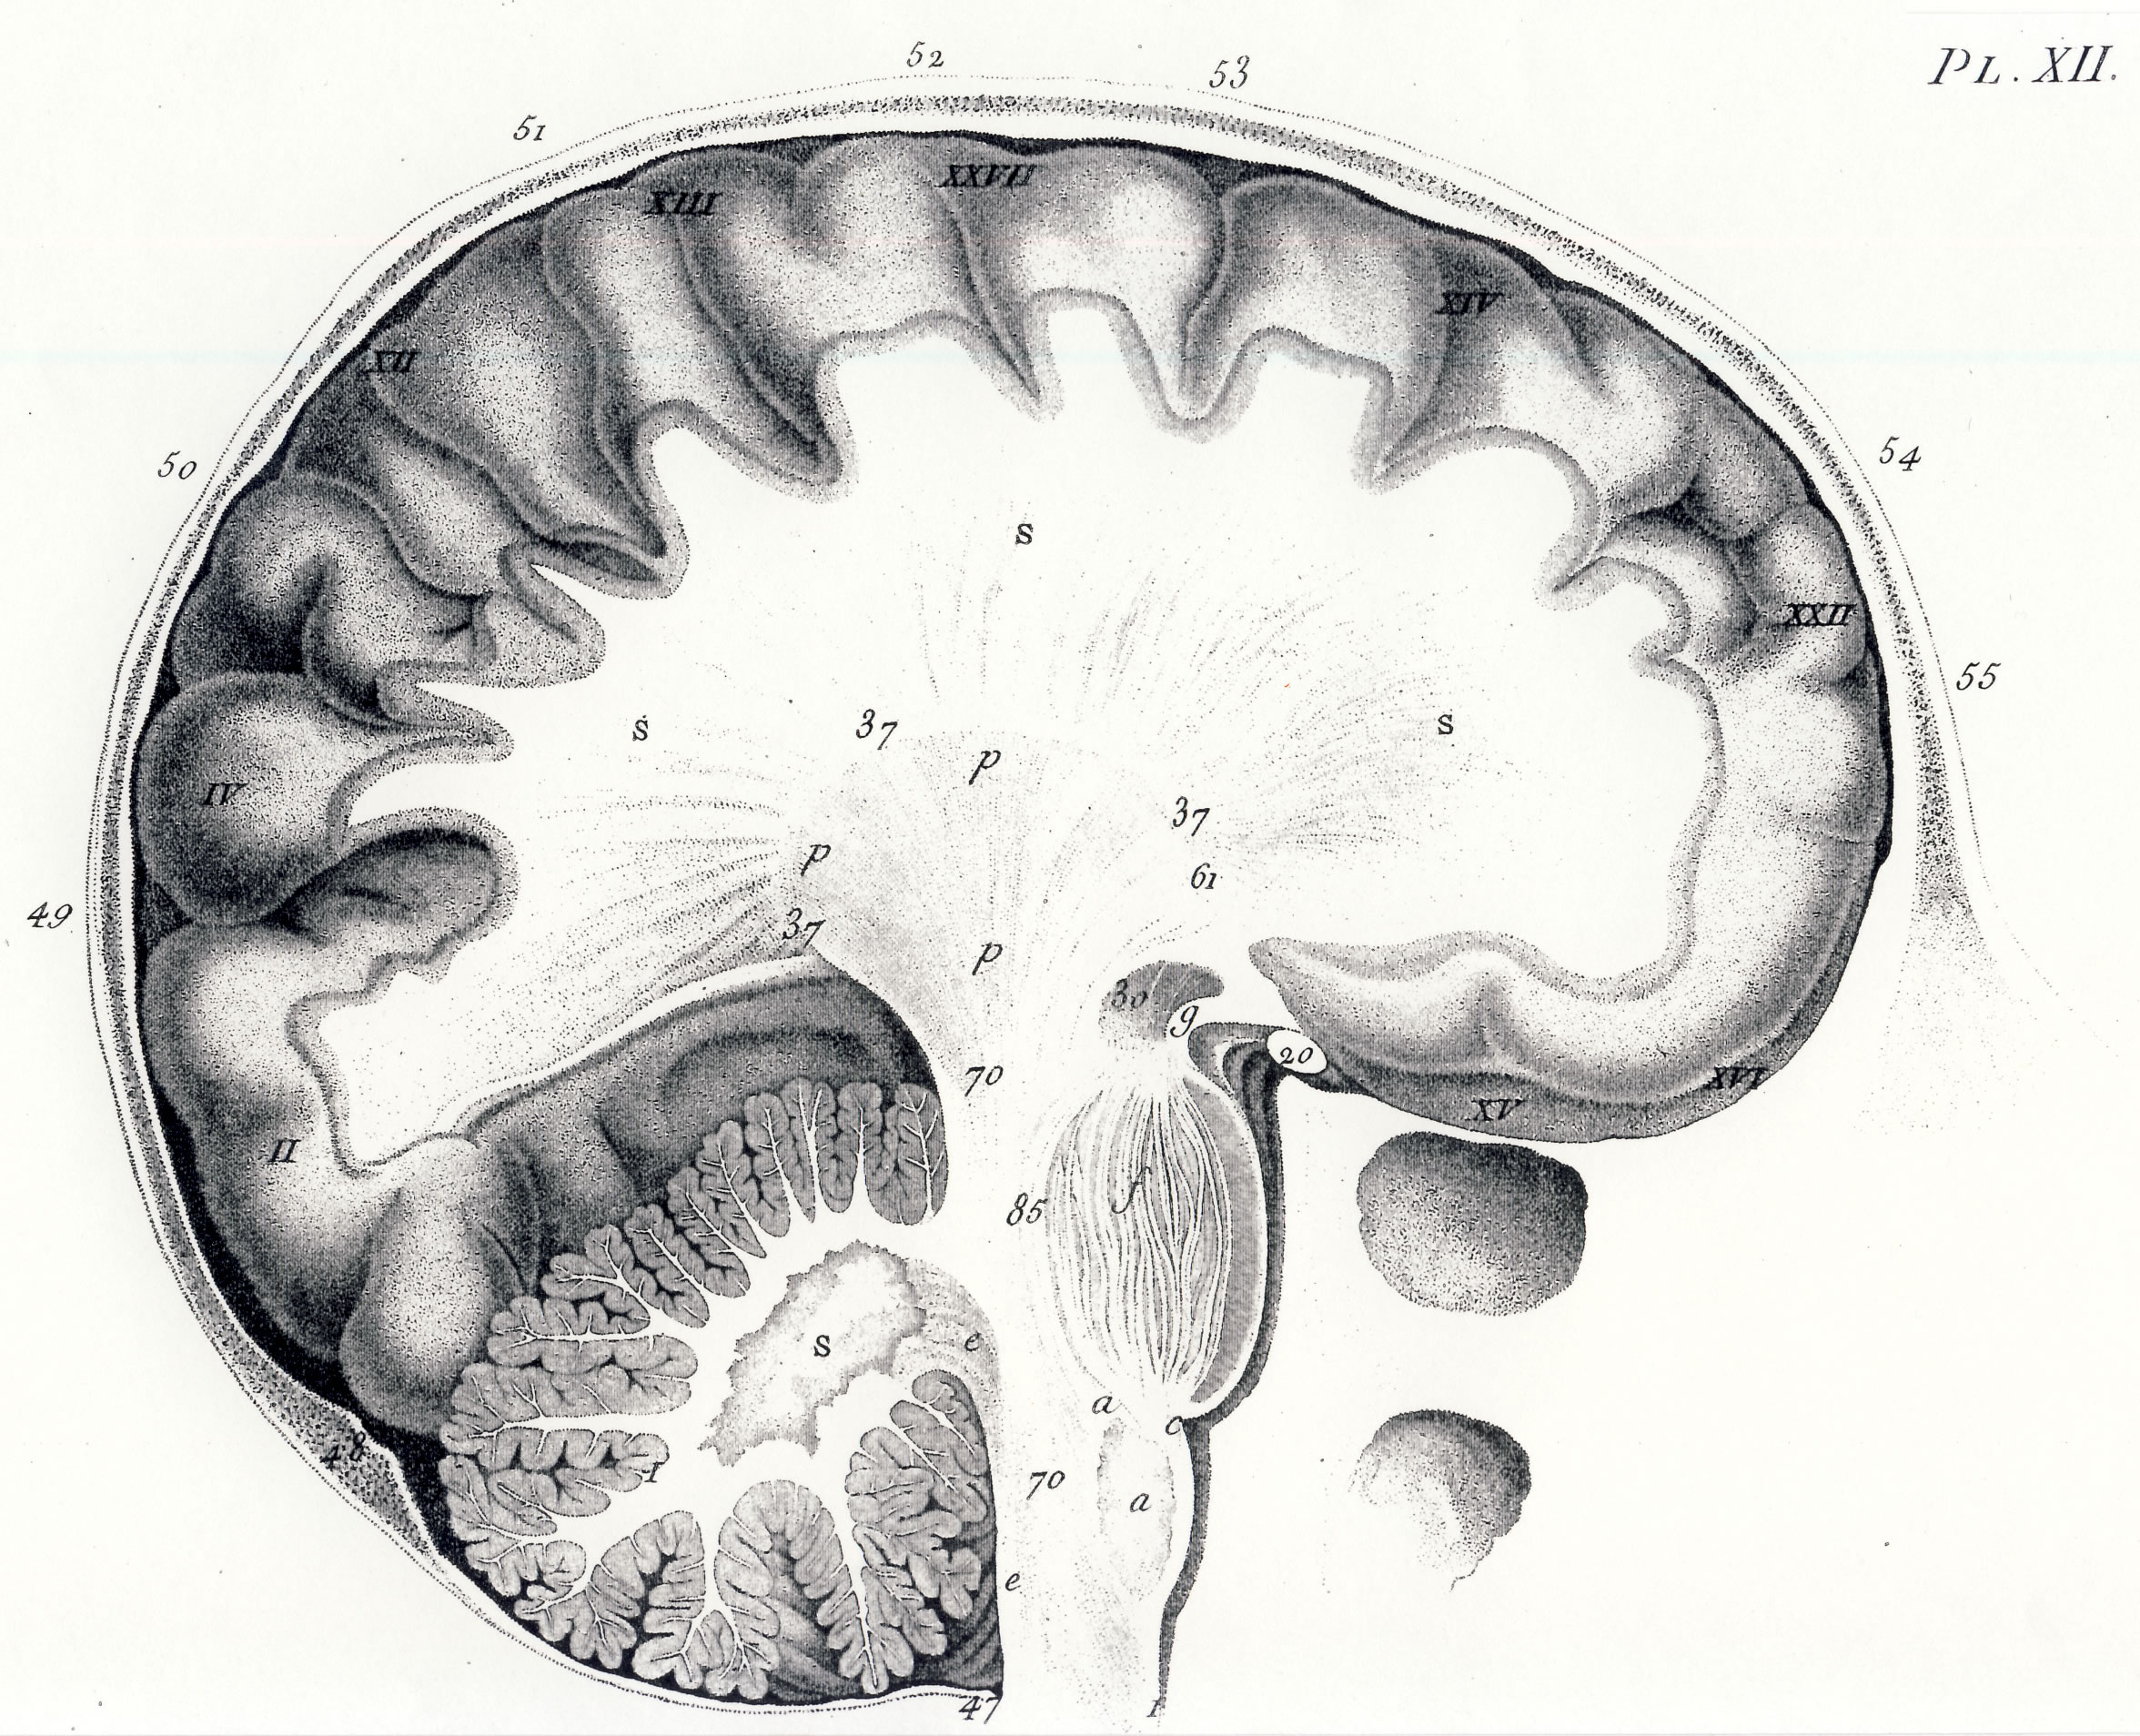

Gall, F. J. (1818). Anatomie et physiologie du système nerveux en général, et du cerveau en particulier, Avec des observations sur la possibilité de reconnoître plusieurs dispositions intellectuelles et morales de l´homme et des animaux, par la configuration de leurs têtes.

Librairie Grecque-Latine-Allemande, Vol. 3, I-XXXV u. 1-379 100 planches.